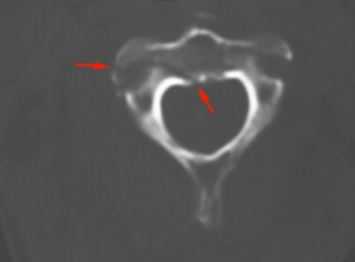

(Справа) На аксиальном GRE МР-И у пациента с флексионной травмой шейного отдела позвоночника видно массивное паренхиматозное кровоизлияние в центральной части спинного мозга, характеризующееся в этом режиме низкой интенсивностью сигнала. Такая картина является плохим прогностическим признаком возможности полноценного функционального восстановления. (Слева) Рентгенограмма в боковой проекции: расширение промежутка между остистыми отростками С6 и С7. Нижний суставной отросток С6 находится впереди верхнего суставного отростка С7.

(Справа) КТ, аксиальный срез: пациент с тяжелой флексионной травмой шейного отдела позвоночника с подвывихом позвонков видны признаки оскольчатого перелома тела и задних элементов позвонка со смещением суставных отростков. (Слева) Т2-ВИ, сагиттальная проекция: признаки антелистеза С7 с расхождением остистых отростков С7-Т1 отеком межостистой связки и спинного мозга.

(Справа) КТ, аксиальный срез с КУ: пациент с флексионной травмой шейного отдела позвоночника с «сцепившимся вывихом», нижние суставные отростки С6 располагаются впереди верхних суставных отростков С7 (такая рентгенологическая картина носит название признака «обнаженных фасеток» или признака «гамбургера»).